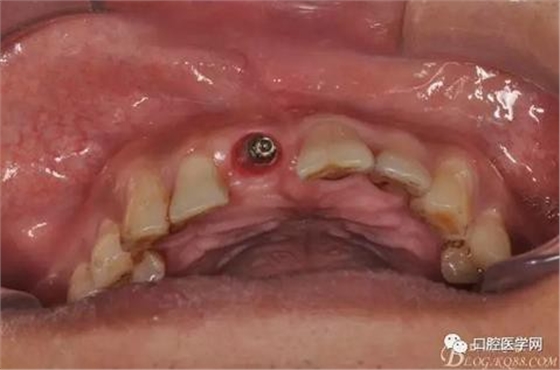

圖6 術中植入植體

圖7 術后植入愈合基

圖8 術后即刻臨時冠修復

圖10 三個月后袖口形成頜面照